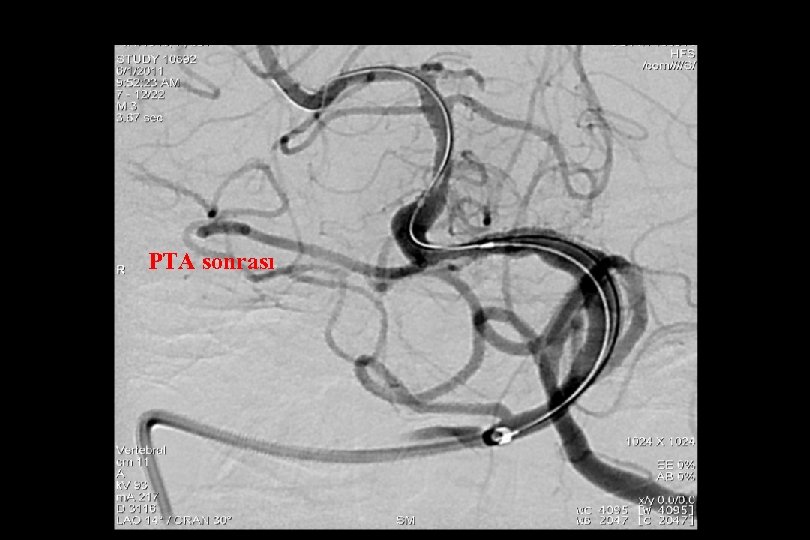

71 y kadın hasta En iyi medikal tedavi altında post fossa iskemik ataklara neden olan baziler stenoz

Sağ brakial yaklaşım ile Reflex /Navien servikal R- VA’e ve intrakraniyal segmente ilerletilmiştir.

• • • Distal Giriş Kateterleri Exchange in minumuma indirilmesi (primer gateway le bypass veya Reflex ve monorail balonla bypass pta balon Mikrokateterden bırakılan stent kullanılması

PTA sonrası

. . 6 mm Solitaire ile Stentleme sonrası